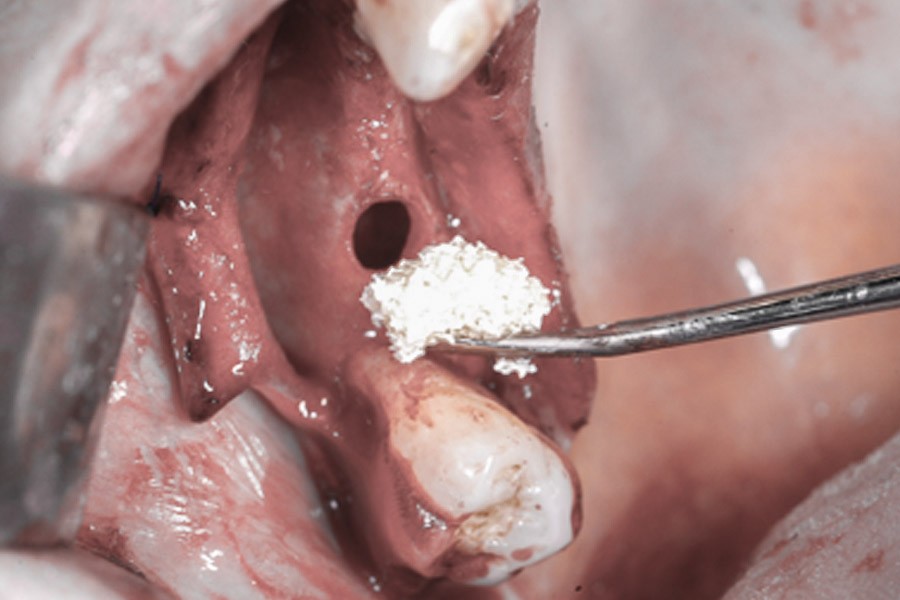

Zabieg odbudowy zębodołu powinno się wykonać możliwe jak najszybciej po usunięciu zęba. Jego celem jest odbudowa naturalnej objętości kości w miejscu utraconego zęba, a następnie szybkie wprowadzenie implantu. Najlepsze rezultaty uzyskuje się przy zastosowaniu biomateriału w formie bloczków kolagenowych lub granulatu, które dają trwałe efekty odbudowy oraz optymalną funkcję i estetykę odtworzonych koron zębów na wszczepionym implancie.

Materiał kościotwórczy występuje zazwyczaj w formie granulatu o różnej grubości drobin. Może być materiałem odzwierzęcym, syntetycznym lub homogennym. W Polsce statystycznie najczęściej używane są materiały pochodzenia odzwierzęcego pozyskane od zwierząt kręgowych. Usypany do ubytku ma on za zadanie stworzenie mineralnego szkieletu dla odbudowującej się tkanki kostnej. W trakcie jej tworzenia materiał ulega integracji z tkanką pacjenta.

Bloki kolagenowe używane są najczęściej do odbudowy geometrycznych, trójwymiarowych ubytków kostnych, których doskonałym przykładem jest zębodół po ekstrakcji zęba. Jest to jeden ze sposobów na procedurę „socket preservation”, czyli natychmiastową lub wczesną odbudowę zębodołów poekstrakcyjnych dla osiągnięcia optymalnych efektów estetycznej odbudowy protetycznej koron zębów na implantach.